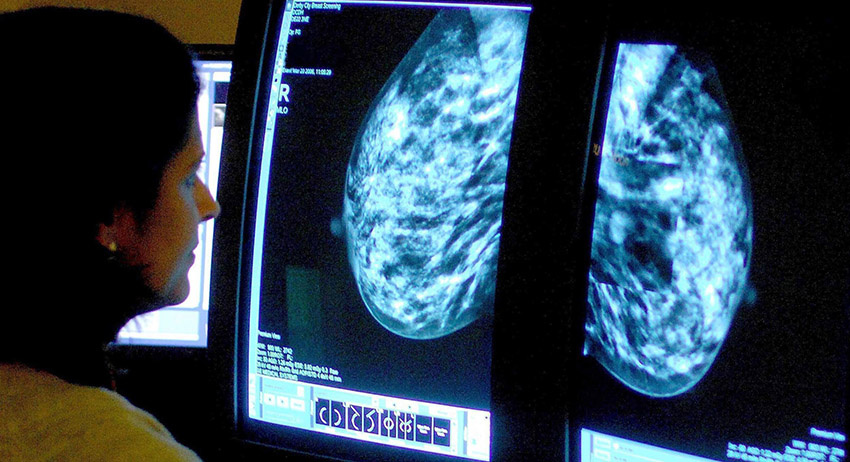

Возникновение рака груди связали с алкоголем

Фото: Rui Vieira/PA Images/TASS

Медики назвали основные причины появления рака груди. На процесс возникновения опухоли могут повлиять ожирение и злоупотребление алкоголем. Учёные провели более шести исследований, в которых приняли участие свыше двухсот тысяч женщин.